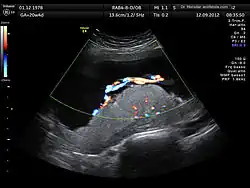

Ultrasound image of human placenta and umbilical cord (color Doppler rendering) with central cord insertion and three umbilical vessels, at 20 weeks of pregnancy